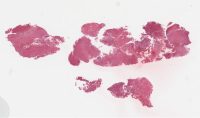

AANP2006-3.svs

54455 x 39431

@ 20X